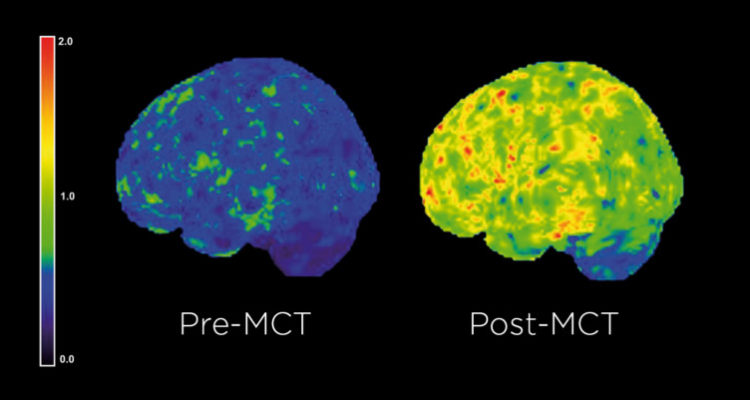

MCT v destilovanej forme majú unikátnu vlastnosť aktivácie tvorby ketónov, vďaka čomu viete efektívnejšie začať spaľovať tuky aj bez potreby dlhšej a náročnej adaptácie na tukový metabolizmus a nízkosacharidovú až ketogenickú stravu. MCT olej sa tak považuje za jeden z najefektívnejších zdrojov energie a doplnok výživy nie len pre telo, ale hlavne pre mozog. Jeho metabolická dráha je veľmi rýchla a bez záťaže žlčníka sa v pečeni konvertujú priamo na ketóny, ktoré za vybraných podmienok dokážu výborne dodať energiu pre mozog.

Zo súčasných nových poznatkov o metabolizme a ketónoch vyplýva, že ketóny sú efektívnejším zdrojom energie pre mozog ako glukóza. (Vid referencie dole)

Study Shows How Bulletproof Brain Octane C8 MCT Oil Powers the Brain